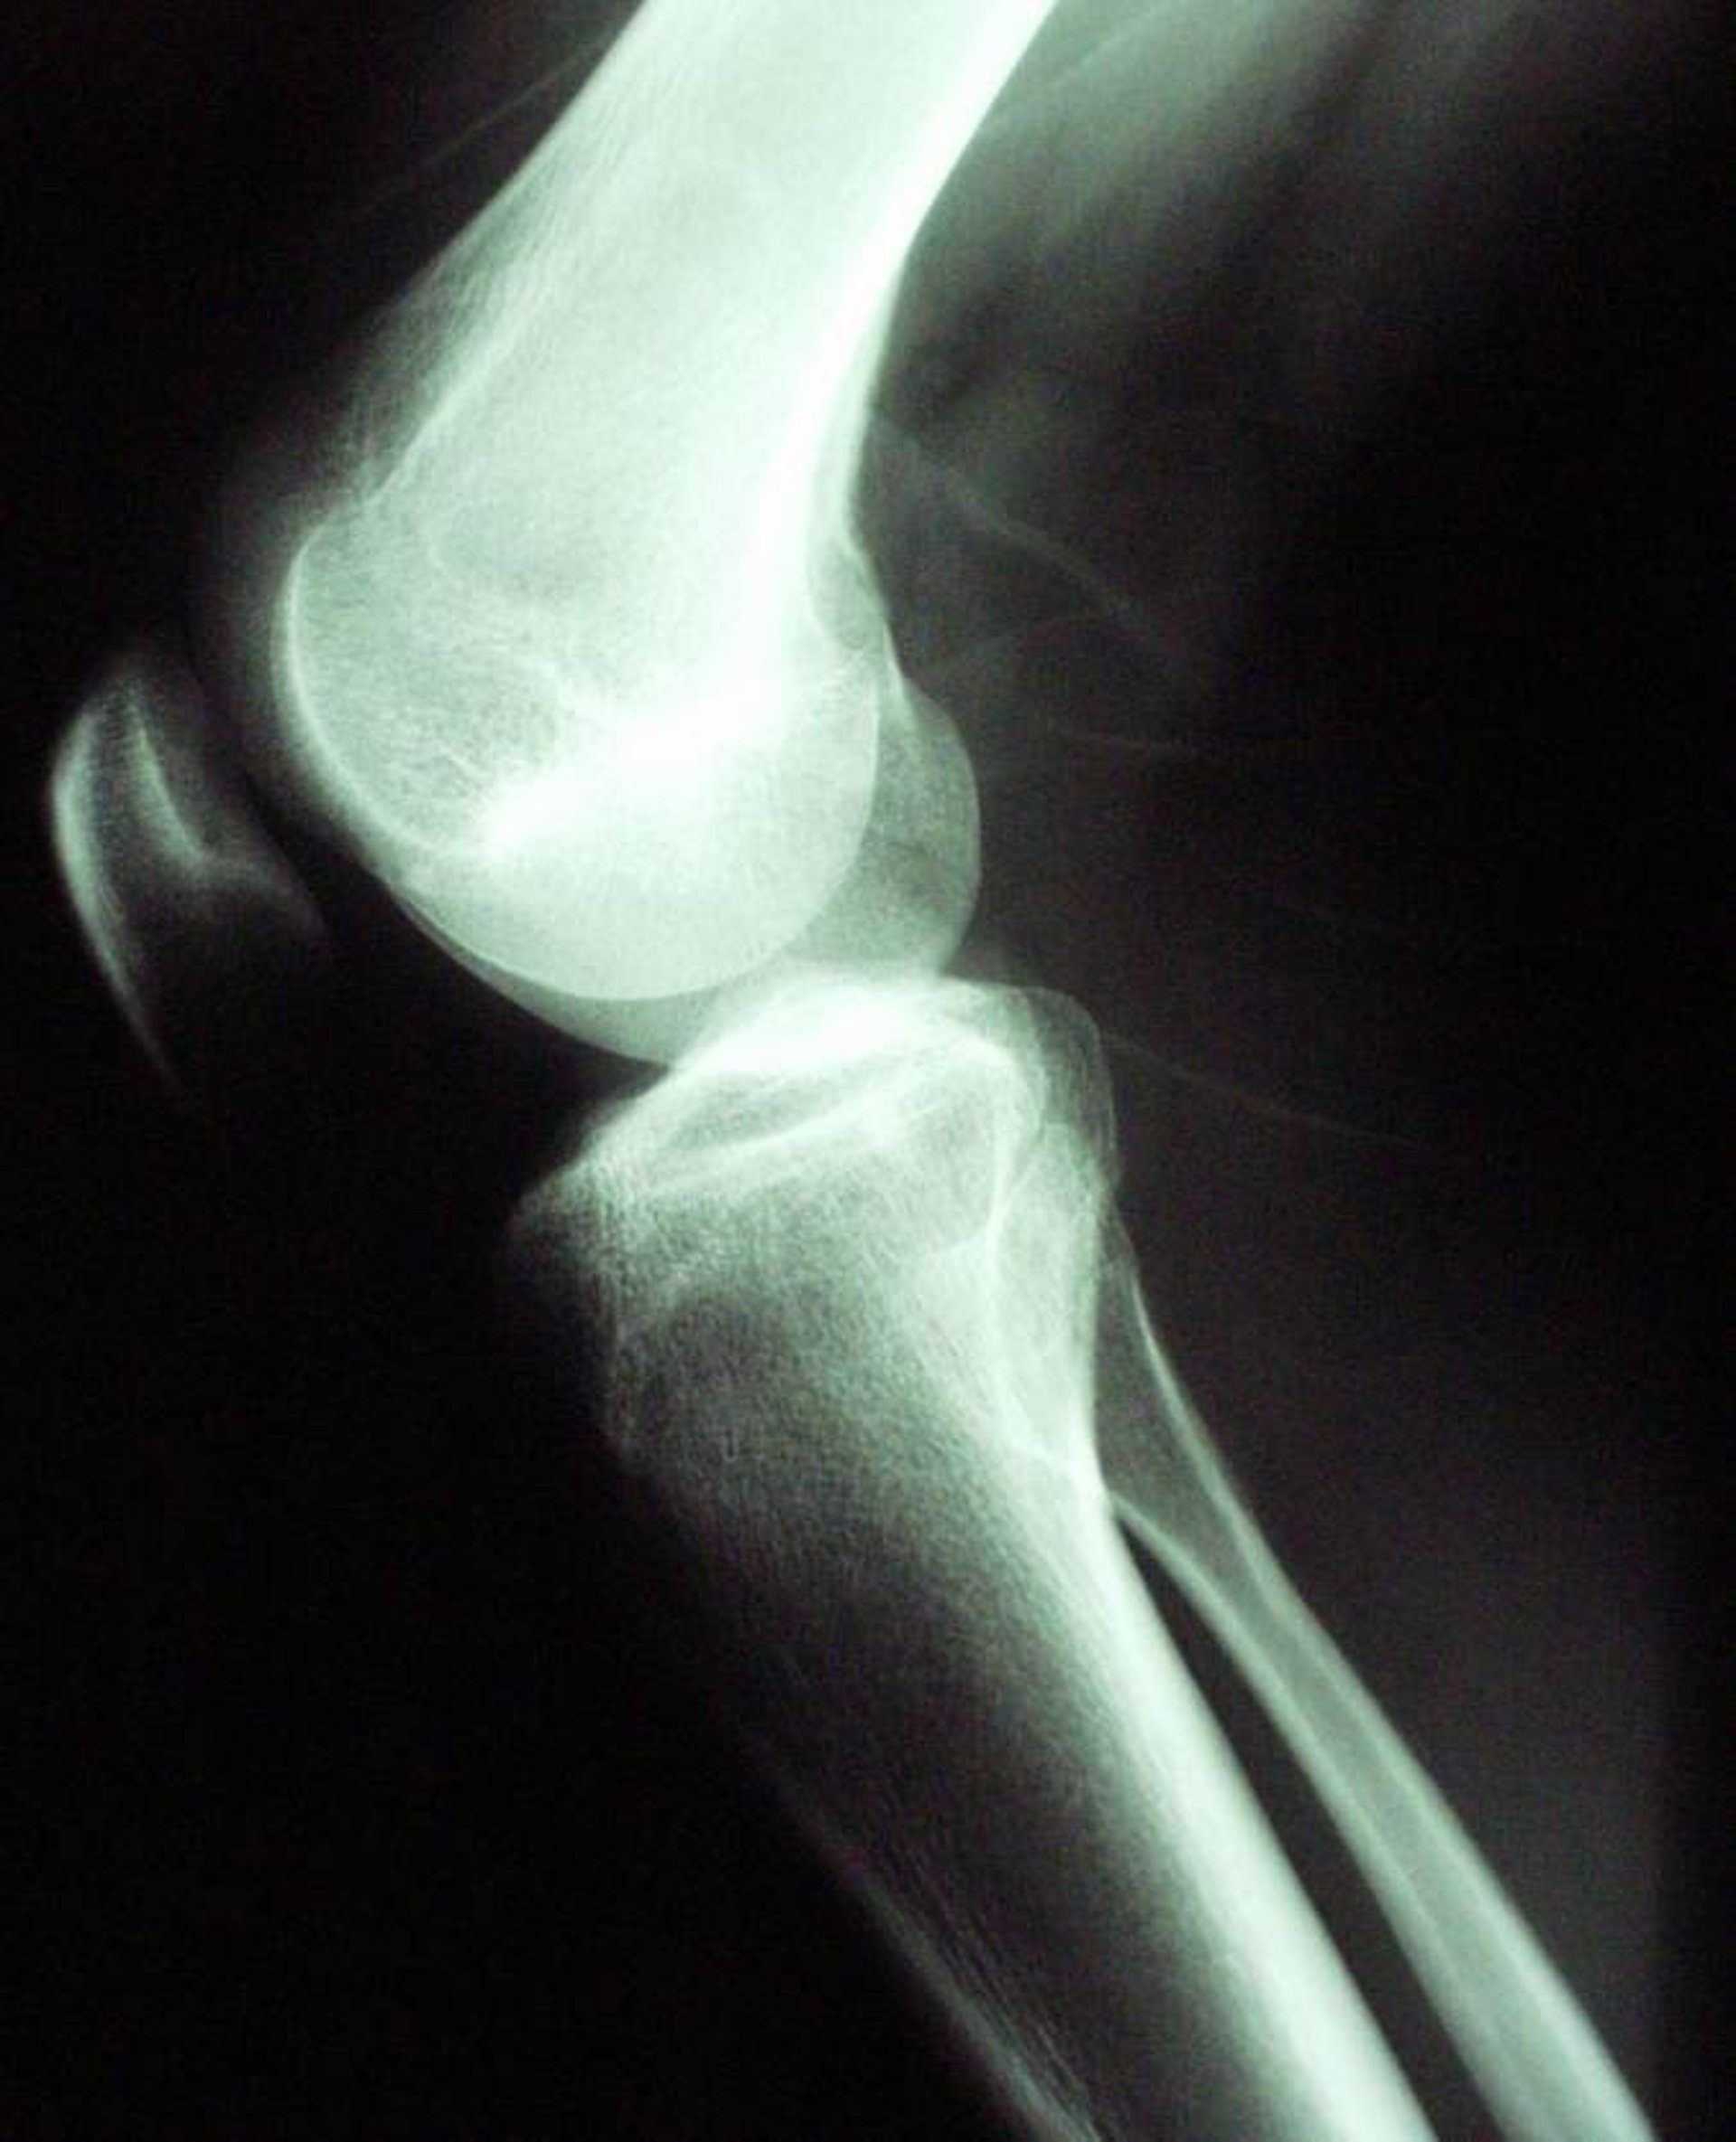

Rodilla, radiografía

WIKIMEDIA/ ABFOTOGRAFIERTES RÖNTGENBILD